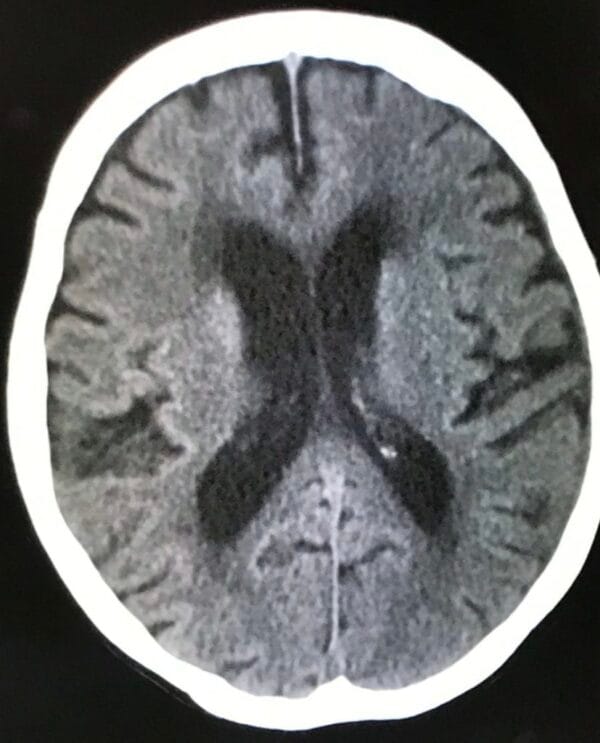

次に、8月下旬、同医師から時々意識・記憶が薄くなりボーッとしていることがあり心配なので、救急外来に行って詳しい検査を受けて欲しいとの連絡。

8月27日に大雨の中、検査を受けに行き、翌日28日に、慢性硬膜下血腫の疑いがあると診断。

特に治療は行わず、1カ月程度後に再度検査を行うということで、再診予約。

9月25日に再度検査をした結果、血腫は消えており、一過性のものだったと。一件落着。

※8月27日撮影画像

※9月25日再撮影画像:上の画像の右周縁部にある陰が消えている